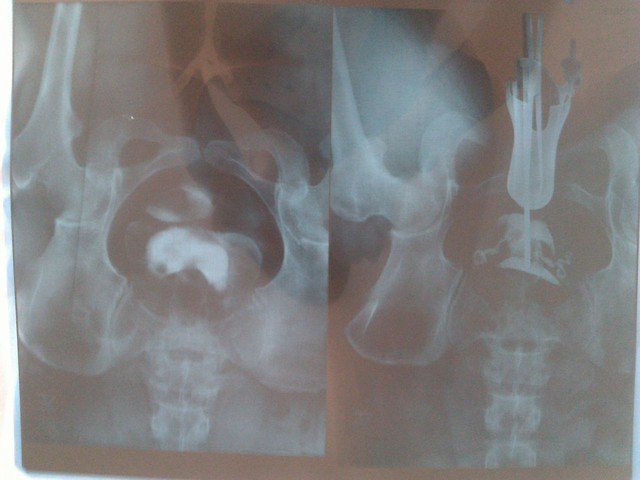

帮忙看下输卵管造影片是什么问题,通吗?

输征助顿卵管,好像是亲之通畅的,多年不孕,很可能是多囊引起,可采用药物调理,一般一个月左右即可以试孕。尺稼

片子不清晰,还放倒了,建议从新发。我帮你看看。